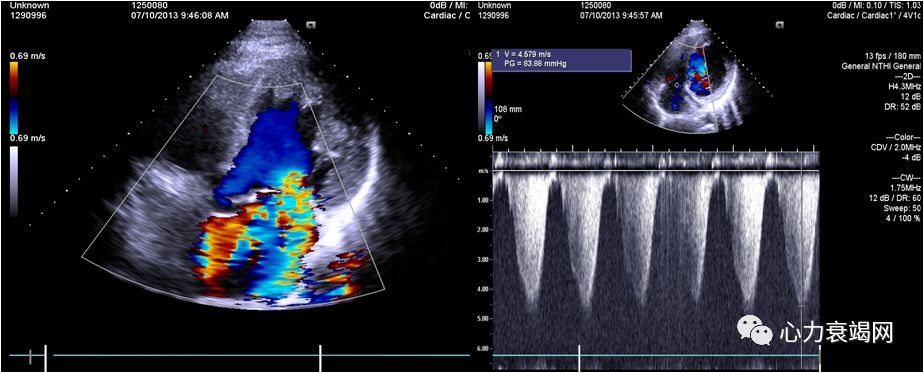

➤ 全心扩大(左房内径41mm,左室内径(d)70mm,(s)58mm)

➤ LVEF36%,肺动脉血流未见异常

➤ 二尖瓣收缩期见轻微返流

➤ 室间隔厚09mm,左室后壁厚10mm

为什么心力衰竭症状再发?

为什么心脏再次扩大?

自行停服任何药物1年

吸烟

饮酒

肺部感染

心肌病?